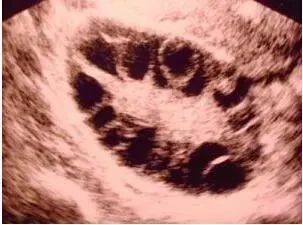

(B超显示多囊患者卵巢中有十多个发育不成熟的小卵泡)